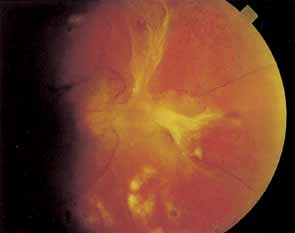

PROLIFERATIVE DIABETIC RETINOPATHY

Proliferative vessels usually arise from veins and often begin as a collection of fine vessels. When they arise on or within 1 disc diameter of the optic disc they are referred to as neovascularization of the disc (NVD) (Fig. 9). When they arise further than 1 disc diameter away, they are called neovascularization elsewhere (NVE) (Fig. 10). NVE nearly always grows toward and into zones of retinal capillary nonperfusion, but capillary nonperfusion is nearly always more widespread in eyes with NVD than it is in NVE.12 Interestingly, it is seen more often in patients younger than 40 compared to older patients with diabetes.13

Once the stimulus for growth of new vessels is present the vessels grow along the path of least resistance. The absence of the internal limiting membrane over the optic disc could explain the proclivity of new vessel growth at that location. Neovascularization grows readily along connective tissue scaffolding such as the posterior hyaloidal face (Fig. 11).

The new vessels, initially naked, usually progress through a stage of further proliferation with associated connective tissue formation. As PDR progresses, the fibrous component becomes more prominent. Fibrotic tissue can be vascular or avascular. The fibrovascular variety is usually found in association with vessels extending into the vitreous cavity or with abnormal new vessels on the surface of the retina or disc. The avascular variety usually results from organization or thickening of the posterior hyaloid face.

Posterior vitreous detachment in diabetics is characterized by a slow, overall shrinkage of the entire formed vitreous rather than by the formation of cavities caused by vitreous destruction.14 Davis15 has stressed the role of the contracting vitreous in the production of vitreous hemorrhage, retinal breaks, and retinal detachment. Neovascular vessels do not “grow” forward into the vitreous cavity; they are pulled into it by the contracting vitreous to which they are adherent (see Fig. 11). Vitrectomized eyes rarely develop new areas of neovascularization and existent neovascularization tends to regress. If severe enough, posterior vitreous detachment may result in retinoschisis, retinal detachment, and retinal break formation. In eyes fortunate enough not to develop these complications, the neovascularization may burn out, leading to atrophy of the new vessels.

Although the macular edema, exudates, and capillary occlusions seen in NPDR often cause legal blindness, affected patients usually maintain at least ambulatory vision. PDR, on the other hand, often results in severe vitreous hemorrhage or retinal detachment with hand-movements vision or worse. It has long been assumed that sudden vitreous contractions tear the fragile new vessels, causing vitreous hemorrhage. However, 62% to 83% of diabetic vitreous hemorrhages occur during sleep,16,17 possibly because of an increase in blood pressure secondary to early morning hypoglycemia or to rapid eye movement (REM) sleep. Because so few hemorrhages occur during exercise, we do not restrict the activity of patients with proliferative retinopathy. The location of the hemorrhage is important in predicting whether it will clear on its own. If blood is behind the posterior vitreous face it is likely to settle to the bottom of the eye and be absorbed. However, when hemorrhage breaks into formed vitreous it is less likely to clear spontaneously.

A large superficial hemorrhage may separate the internal limiting membrane from the rest of the retina. Such hemorrhages usually are round or oval but may also be boat-shaped (Fig. 12). The blood may remain confined between the internal limiting membrane and the underlying retina for weeks or months before breaking into the vitreous. Subinternal limiting membrane hemorrhages were formerly thought to lie between the internal limiting membrane and the cortical vitreous and were called subhyaloid or preretinal hemorrhages. It is now felt that true subhyaloid hemorrhages are probably quite rare. Tight subinternal limiting membrane hemorrhages are dangerous beause they may progress to traction retinal detachment.18,19

Two types of diabetic retinal detachments occur, those that are caused by traction alone (nonrhegmatogenous) (Fig. 14), and those caused by retinal break formation (rhegmatogenous) (Figs. 15 and 16). Characteristics of nonrhegmatogenous (traction) detachment in PDR include the following: (1) the detached retina is usually confined to the posterior fundus and infrequently extends more than two-thirds of the distancd to the equator, (2) it has a taut and shiny surface, (3) it is concave toward the pupil, and (4) there is no shifting of subretinal fluid.